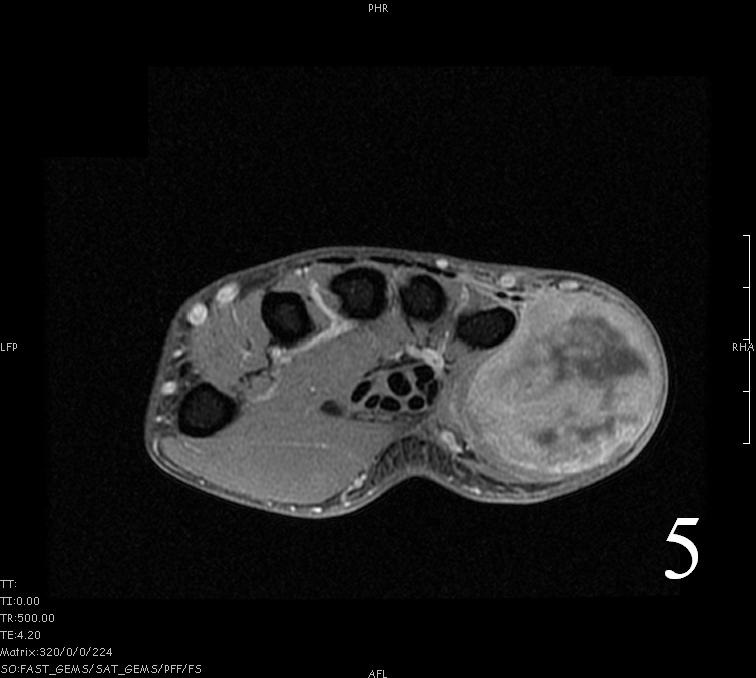

- Isointense to skeletal muscle on T1 (Fig. 4, Fig. 5, Fig. 7, Fig. 8)

Fig. 4-9: MRI of a rhabdomyosarcoma of the hand. The MRI is nonspecific and shows a heterogeneous mass particularly on postgadolinium images T1 W images (Fig. 8) and T2 W images (Fig. 9).